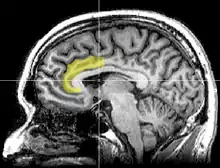

Sagittal MRI slice with highlighting indicating location of the anterior cingulate cortex